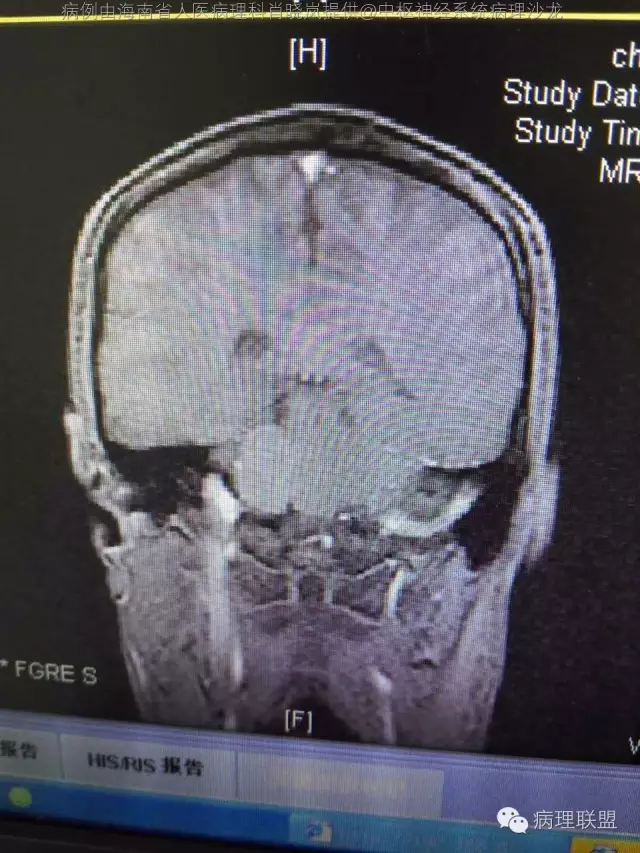

男,36岁。右面部麻木1月余。手术所见:右CPA区见5Ⅹ4cm肿块,灰褐色,血供丰富,质韧,界清。临床诊断:右侧桥小脑角区占位:脑膜瘤。大体检查:灰黑色碎组织一堆,大小2.5Ⅹ2.5x0.5cm,免疫S100,HMB45阳性。Ki67指数低。(病例由海南省人医病理科肖晓岚提供,致谢!)

@海南省人医病理科肖晓岚 影像也是符合黑色素相关肿瘤,可请影像专业的老师分析一下CT结合MR对产生黑色素的病变还是具有一定的特征性的,本例黑色素含量似乎不太多,所以跟脑膜瘤差不太多了,需要请影像老师分析!